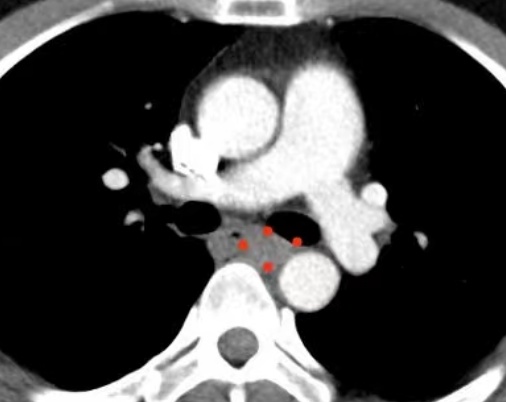

影像表现:纵膈内气管隆突下水平可见软组织密度结节影,密度均匀,其内未见明显钙化灶,该段食管腔略狭窄,尚未见明显阻塞,其上段食管未见扩张,病灶边界光整,增强呈轻度强化。

CT表现:为向腔内或腔外突出的圆形或者半圆形软组织肿块,表面光滑,临近食管壁正常,与周围心包、大血管的界限清晰,同时向腔内外生长的肿块,肿瘤环绕食管壁生长,正常部分食管壁不增厚增强扫描后肿瘤呈均匀轻度强化。